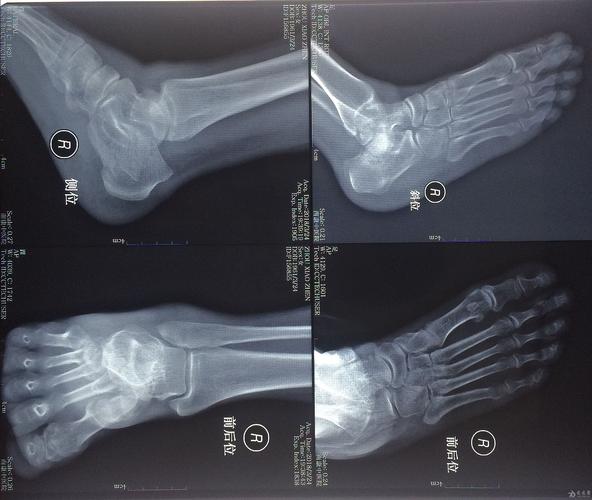

患者,男,17岁,扭伤致右踝关节肿痛活动受限3天.dr及ct如下

脚扭伤了做ct影像表现是,左踝关节在位,关节间隙尚可

左脚脚踝一年前软骨骨折,没有发现,现在里面有一个类似于小骨片的东西